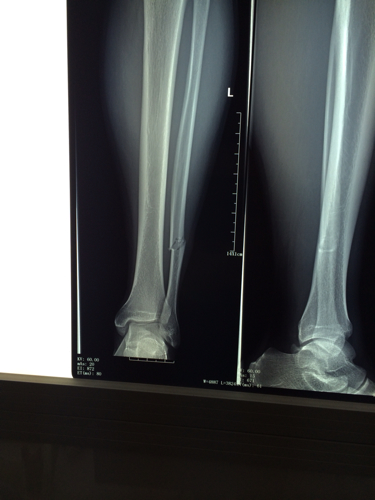

医学影像 摔伤致左小腿下段疼痛,活动受限,x线见腓骨骨折, - 抖音

胫腓骨下段骨折闭合复位髓内钉内固定加腓骨下段锁定钢板内固定手术一

左胫腓骨下端骨折

【病例讨论】左胫骨下段开放性骨折 [病例帖]

小腿左胫腓骨中下段粉碎骨折,保守治疗.